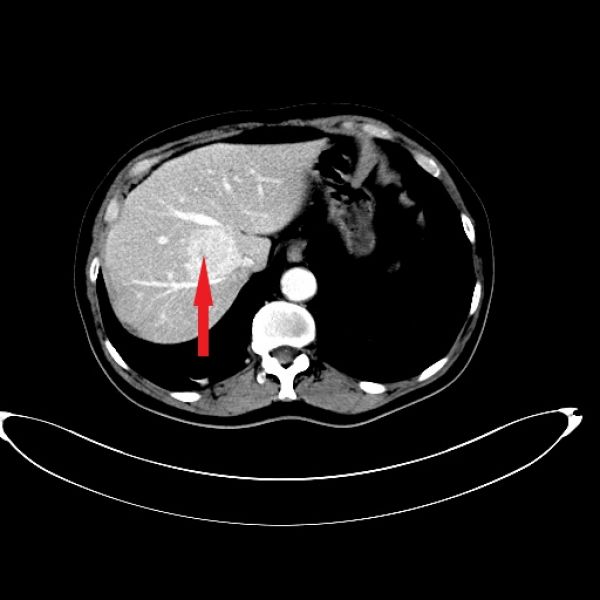

该患者为62岁老年男性,因“体检发现肝占位1天”入院,术前诊断为肝尾状叶局灶性结节样增生(FNH)。完善术前3D成像,评估肿瘤与毗邻血管的关系,经过详细的术前准备,于12月16日在全麻下行腹腔镜尾状叶肿瘤切除术。手术由王文儿副主任医师、陈晓明主治医师及田潭平医师完成。

红色箭头示肿瘤 黄绿红箭头分别示肝右肝中肝左静脉,白色箭头示肿瘤